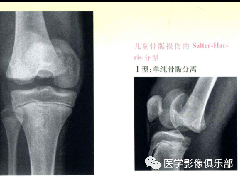

• 儿童骨骺损伤/骨折分型

38种特殊类型的骨折